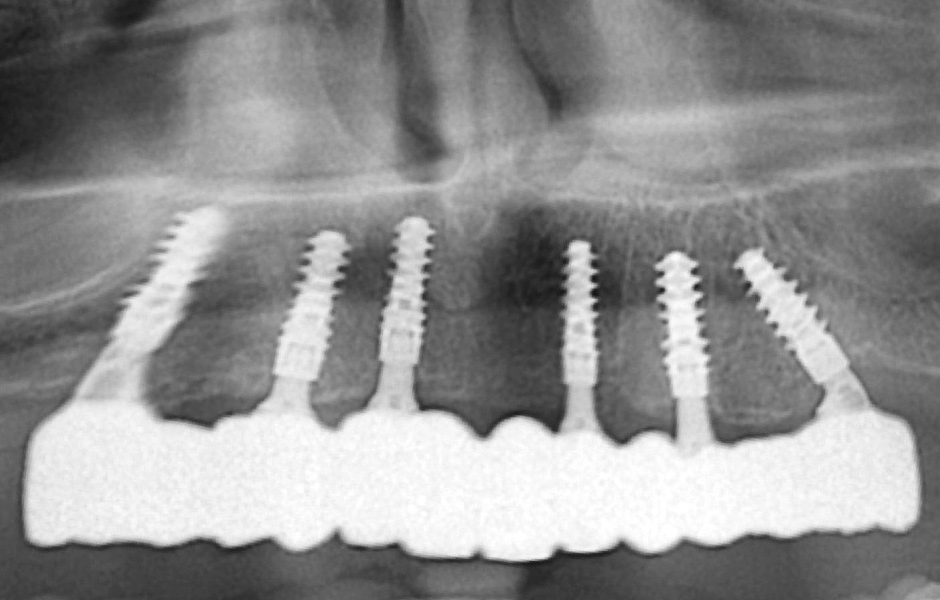

Na základě analýzy panoramatických snímků bylo zjištěno dostatečné vertikální i horizontální množství kosti v dobré kvalitě, proto nebylo zapotřebí provádět řízenou kostní regeneraci (GBR) (obr. 9). Podle klasifikace ITI SAC byl případ hodnocen jako pokročilý až složitý.

Kontrolní rentgenový snímek potvrdil, že jsou všechny klinické parametry v normě (obr. 43).

Definitivní náhrada byla nasazena a ověřena z hlediska estetiky, okluze a funkce (obr. 51–55). Panoramatický kontrolní snímek potvrdil, že všechny parametry protetického ošetření odpovídají očekávaným hodnotám (obr. 56).

Obr. 43

Obr. 56